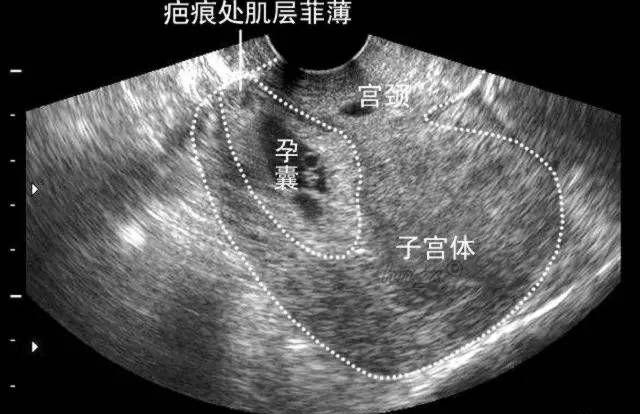

对于已经间隔两年以上、希望继续生育的剖宫产后再妊娠的孕妇,一旦发现怀孕,首先要尽早(最好在早孕6周时)选择有资质的医院做B超,观察胚囊着床的位置与瘢痕的关系,明确胚胎着床的位置是否在剖宫产瘢痕附近以及子宫下段瘢痕处局部血供是否丰富等,这是发现瘢痕妊娠的最快最有效的办法。